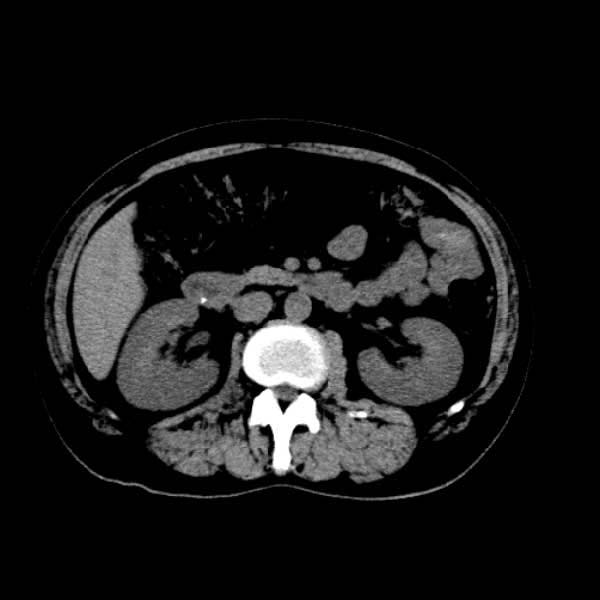

标题: CT13513:男 71 腹部疼痛20余天,近几天高热就诊,骨窗未见异 [打印本页]

标题: CT13513:男 71 腹部疼痛20余天,近几天高热就诊,骨窗未见异

考虑感染性病变可能性大,起源于阑尾?

感染,脓肿形成

考虑为化脓性阑尾炎.脓肿形成.及多肌肉累及.

考虑右侧腰大肌脓肿,向右髂窝、右腹股沟流注。

支持化脓性阑尾炎伴右髂窝脓肿、腰大肌腰方肌脓肿形成。

首先考虑化脓性阑尾炎伴腰大肌、腰方肌脓肿,不除外回盲部结核。

回盲部癌待排除。

患者肠镜检查考虑结肠癌,病理证实

患者肠镜检查考虑结肠癌,病理证实。肺部ct可见多发结节,考虑转移